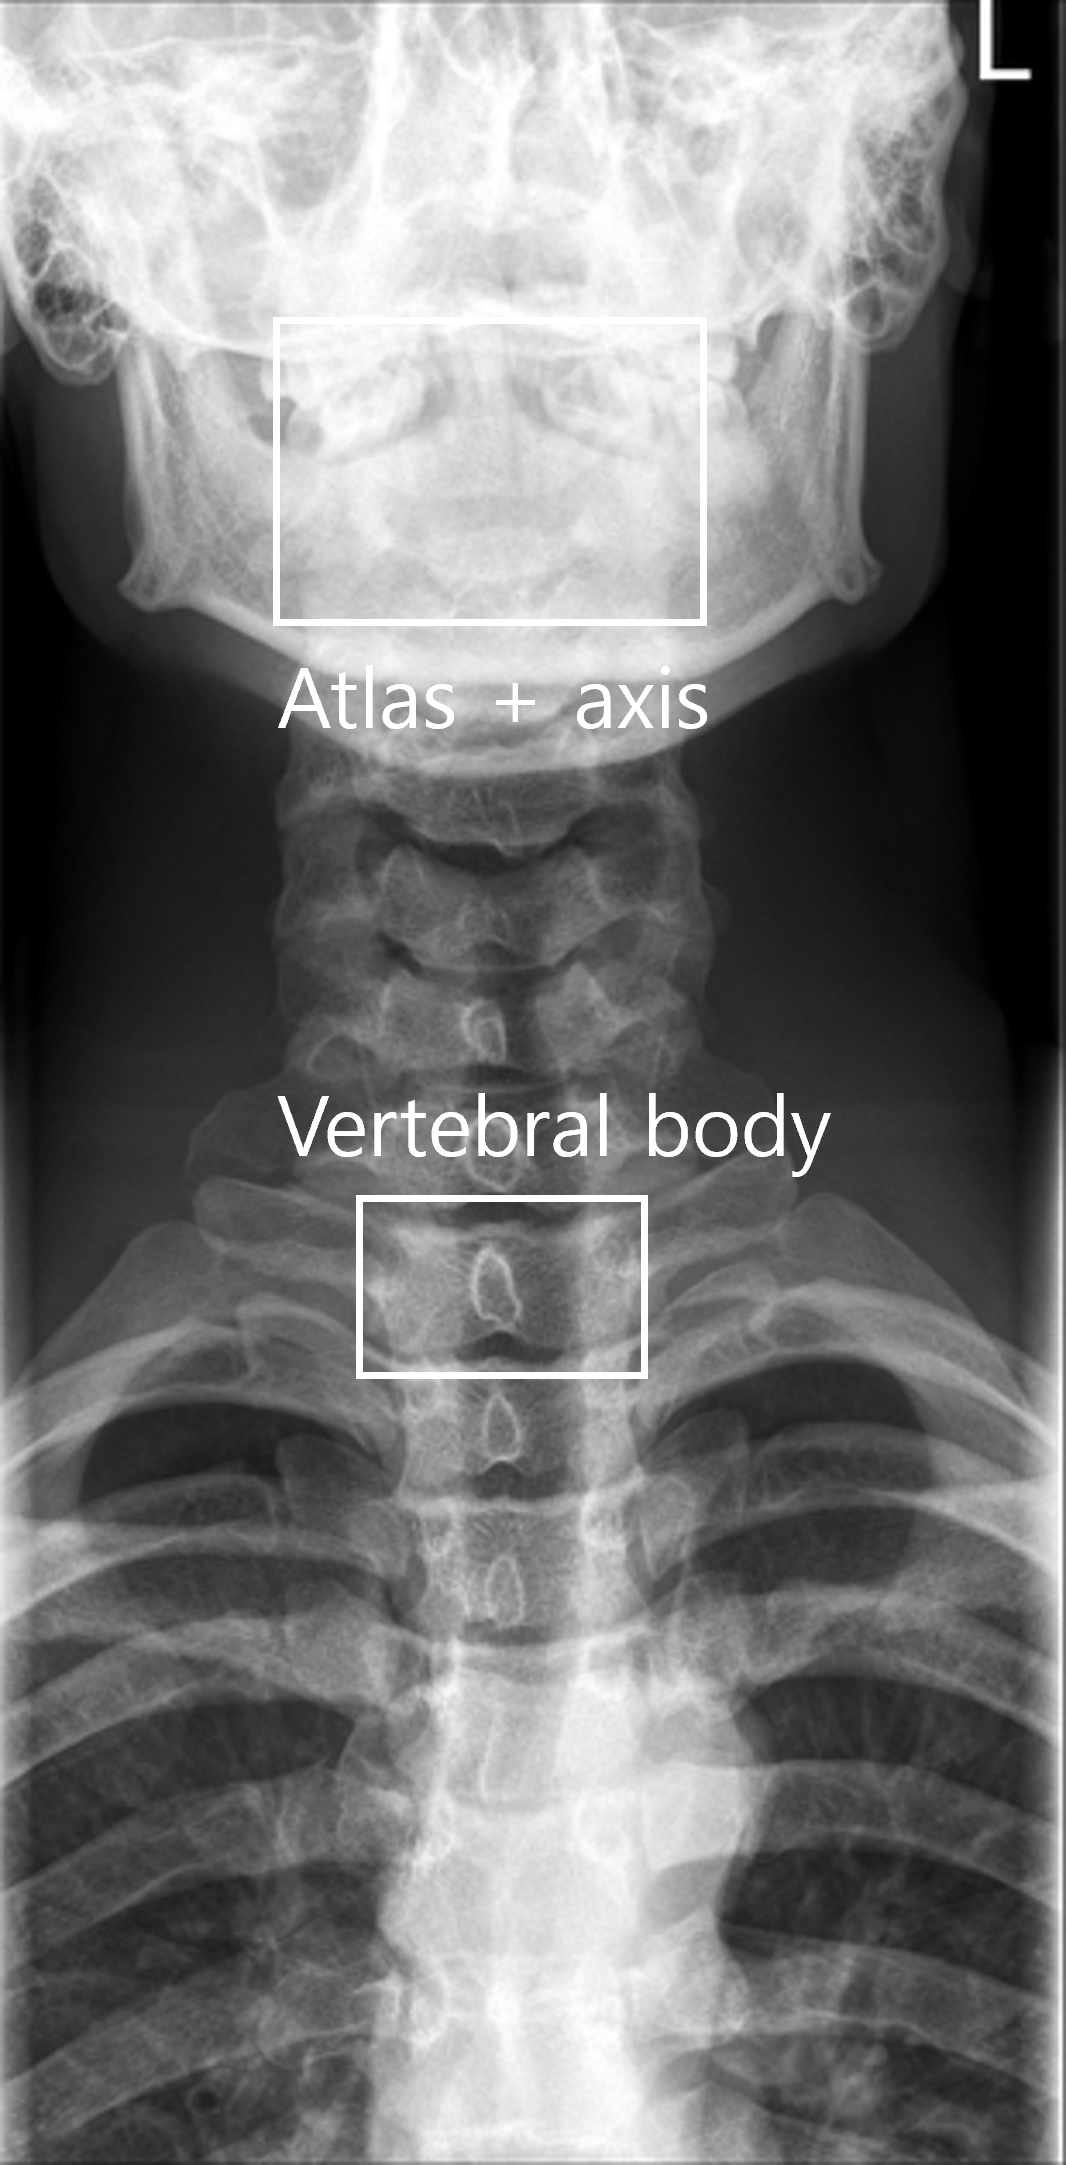

AI 모델이 의료 영상을 효과적으로 학습할 수 있도록, 각 부위와 촬영 방식(AP, Lateral 등)에 맞추어 세그멘테이션(Segmentation), 키포인트(Keypoint), 바운딩 박스(Bounding box) 등 세 가지 방식의 정밀 라벨링 작업을 복합적으로 수행했습니다.

어깨(Shoulder) 및 손목(Wrist): 상완골(humerus), 견봉(acromion), 주상골(scaphoid) 등 구조물을 분할하는 다중 클래스 세그멘테이션(Multi class Segmentation)과 세부 좌표를 지정했습니다.